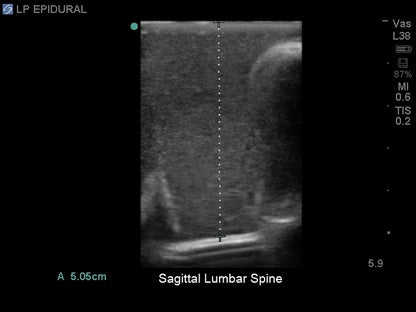

- Ultrasound can be used to identify the optimal insertion points, the angle of needle insertion, and determine the depth to the ligamentum flavum, epidural space, and spine

- Excellent ultrasound imaging properties

- Use any ultrasound system and never have to adjust system settings unrealistically or have trouble imaging the model's anatomy

- Ultra-durable self-healing tissue is extremely realistic in ultrasound imaging properties and feels like real human tissue